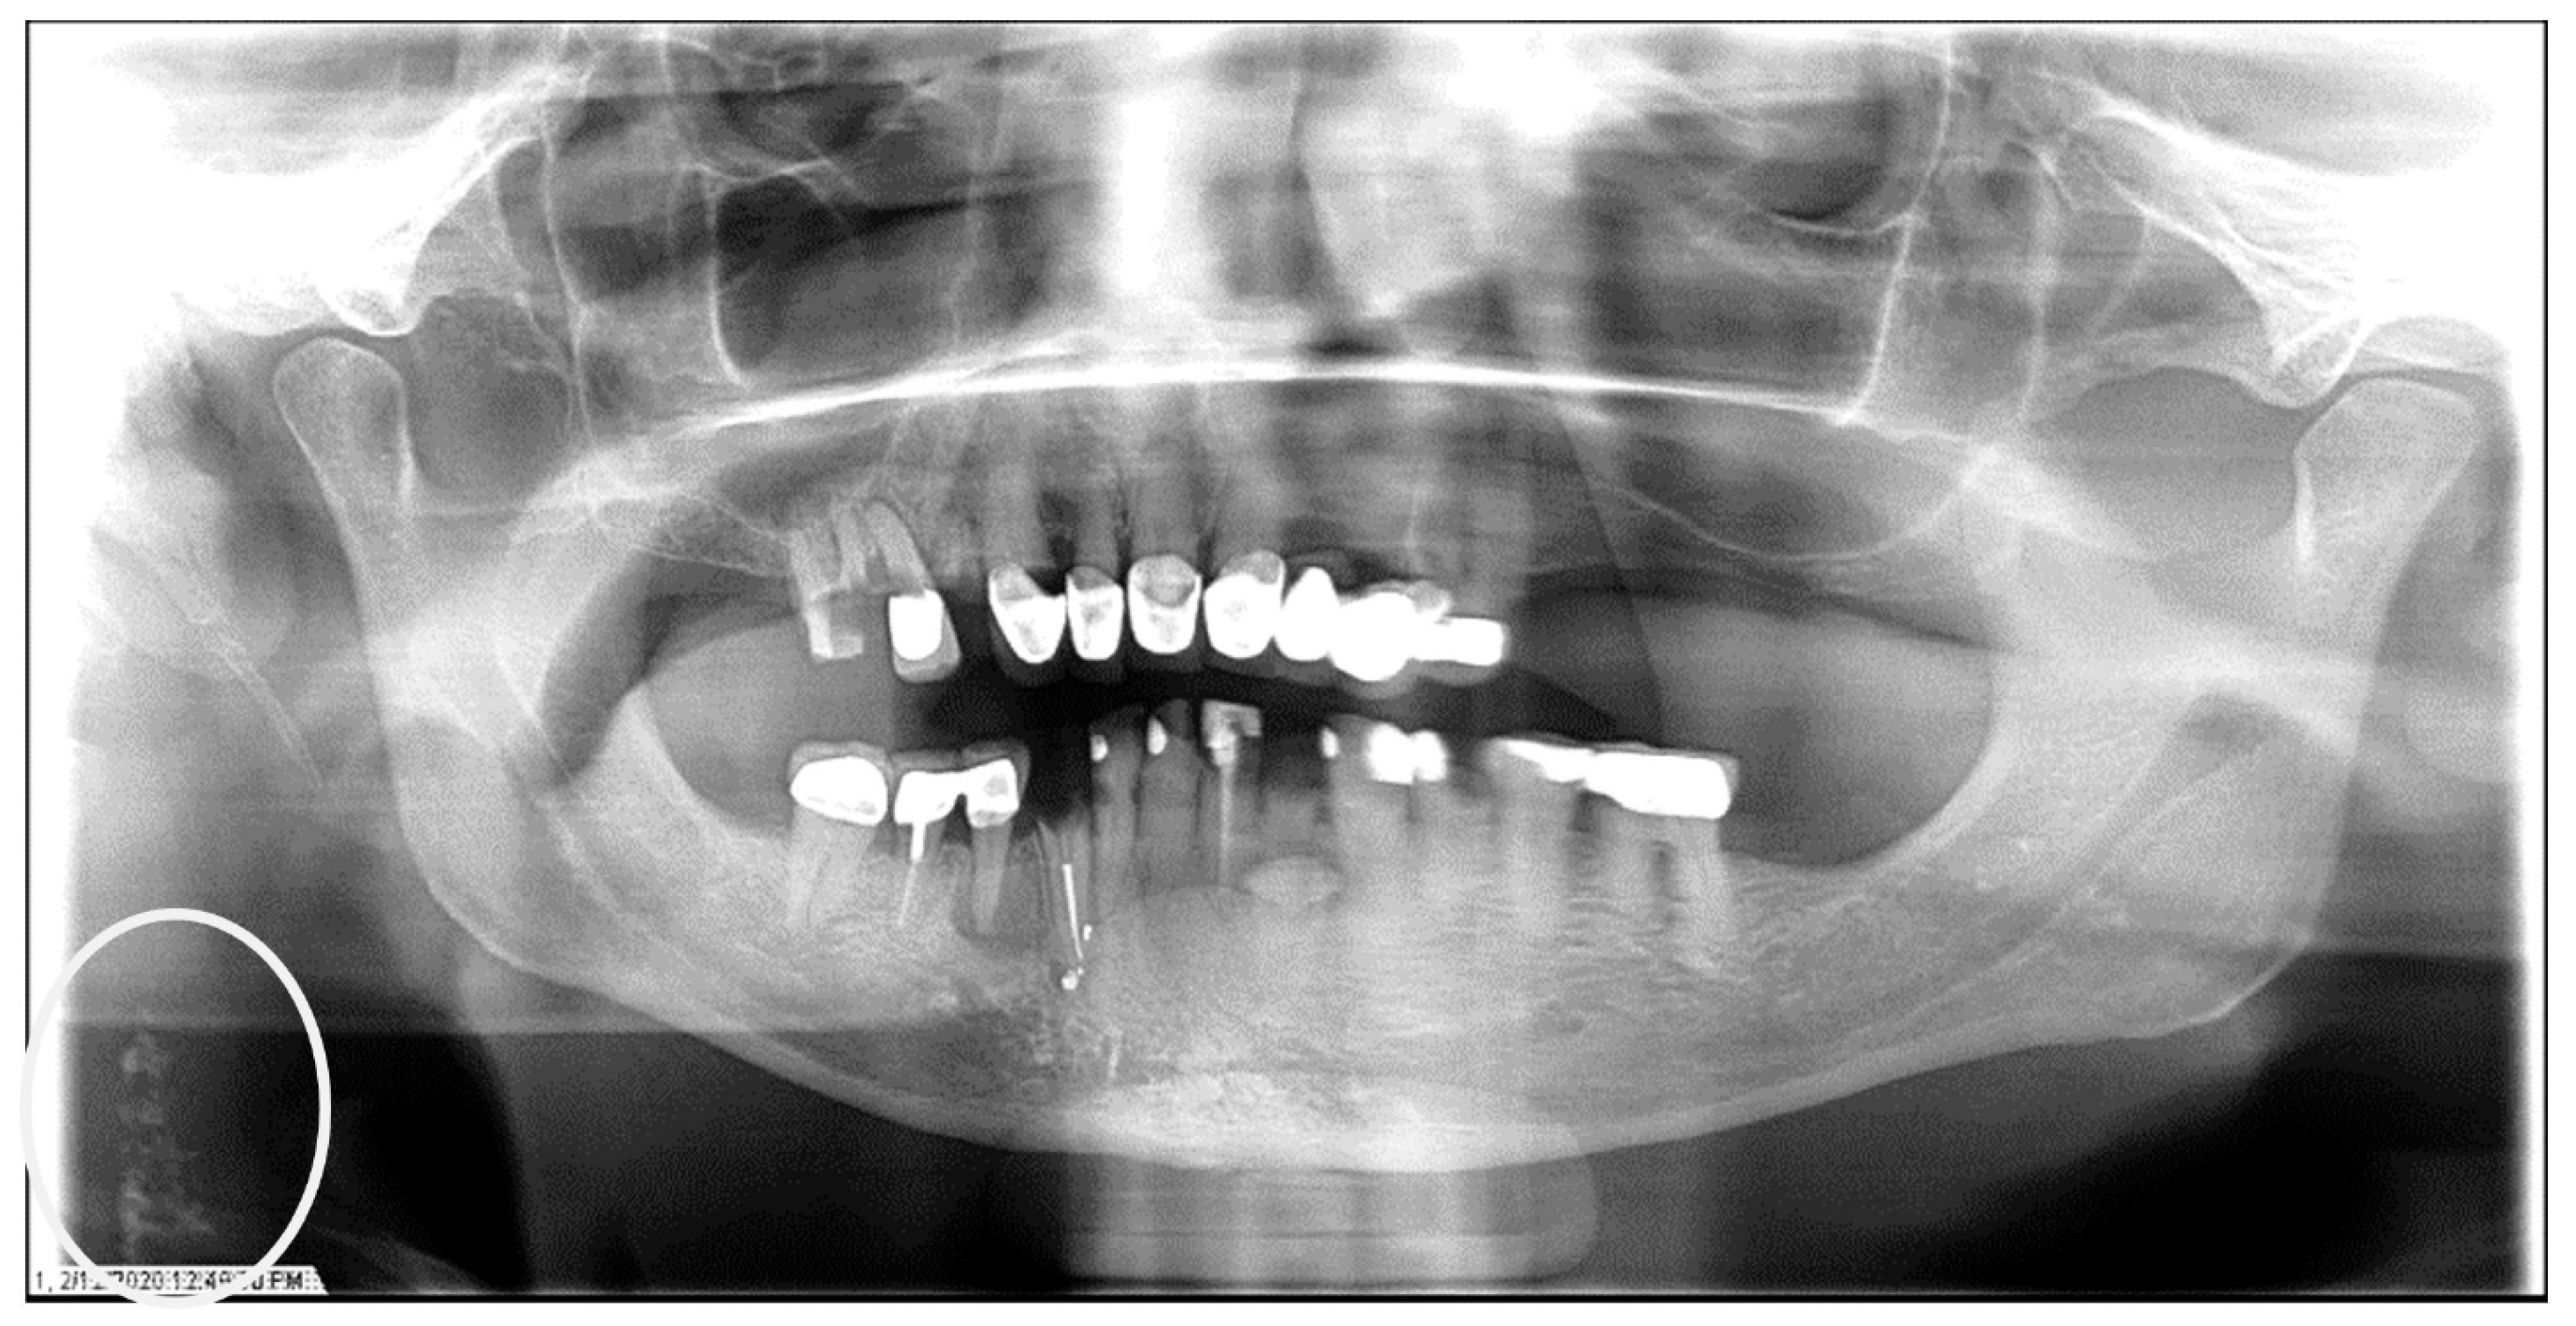

Figure 5.

The panoramic radiograph of a 53-year-old male patient with a medical history of hypertension and hyperlipidemia showing bilateral carotid artery calcifications (CACs) during a comprehensive dental examination. The CACs are encircled by a white line.